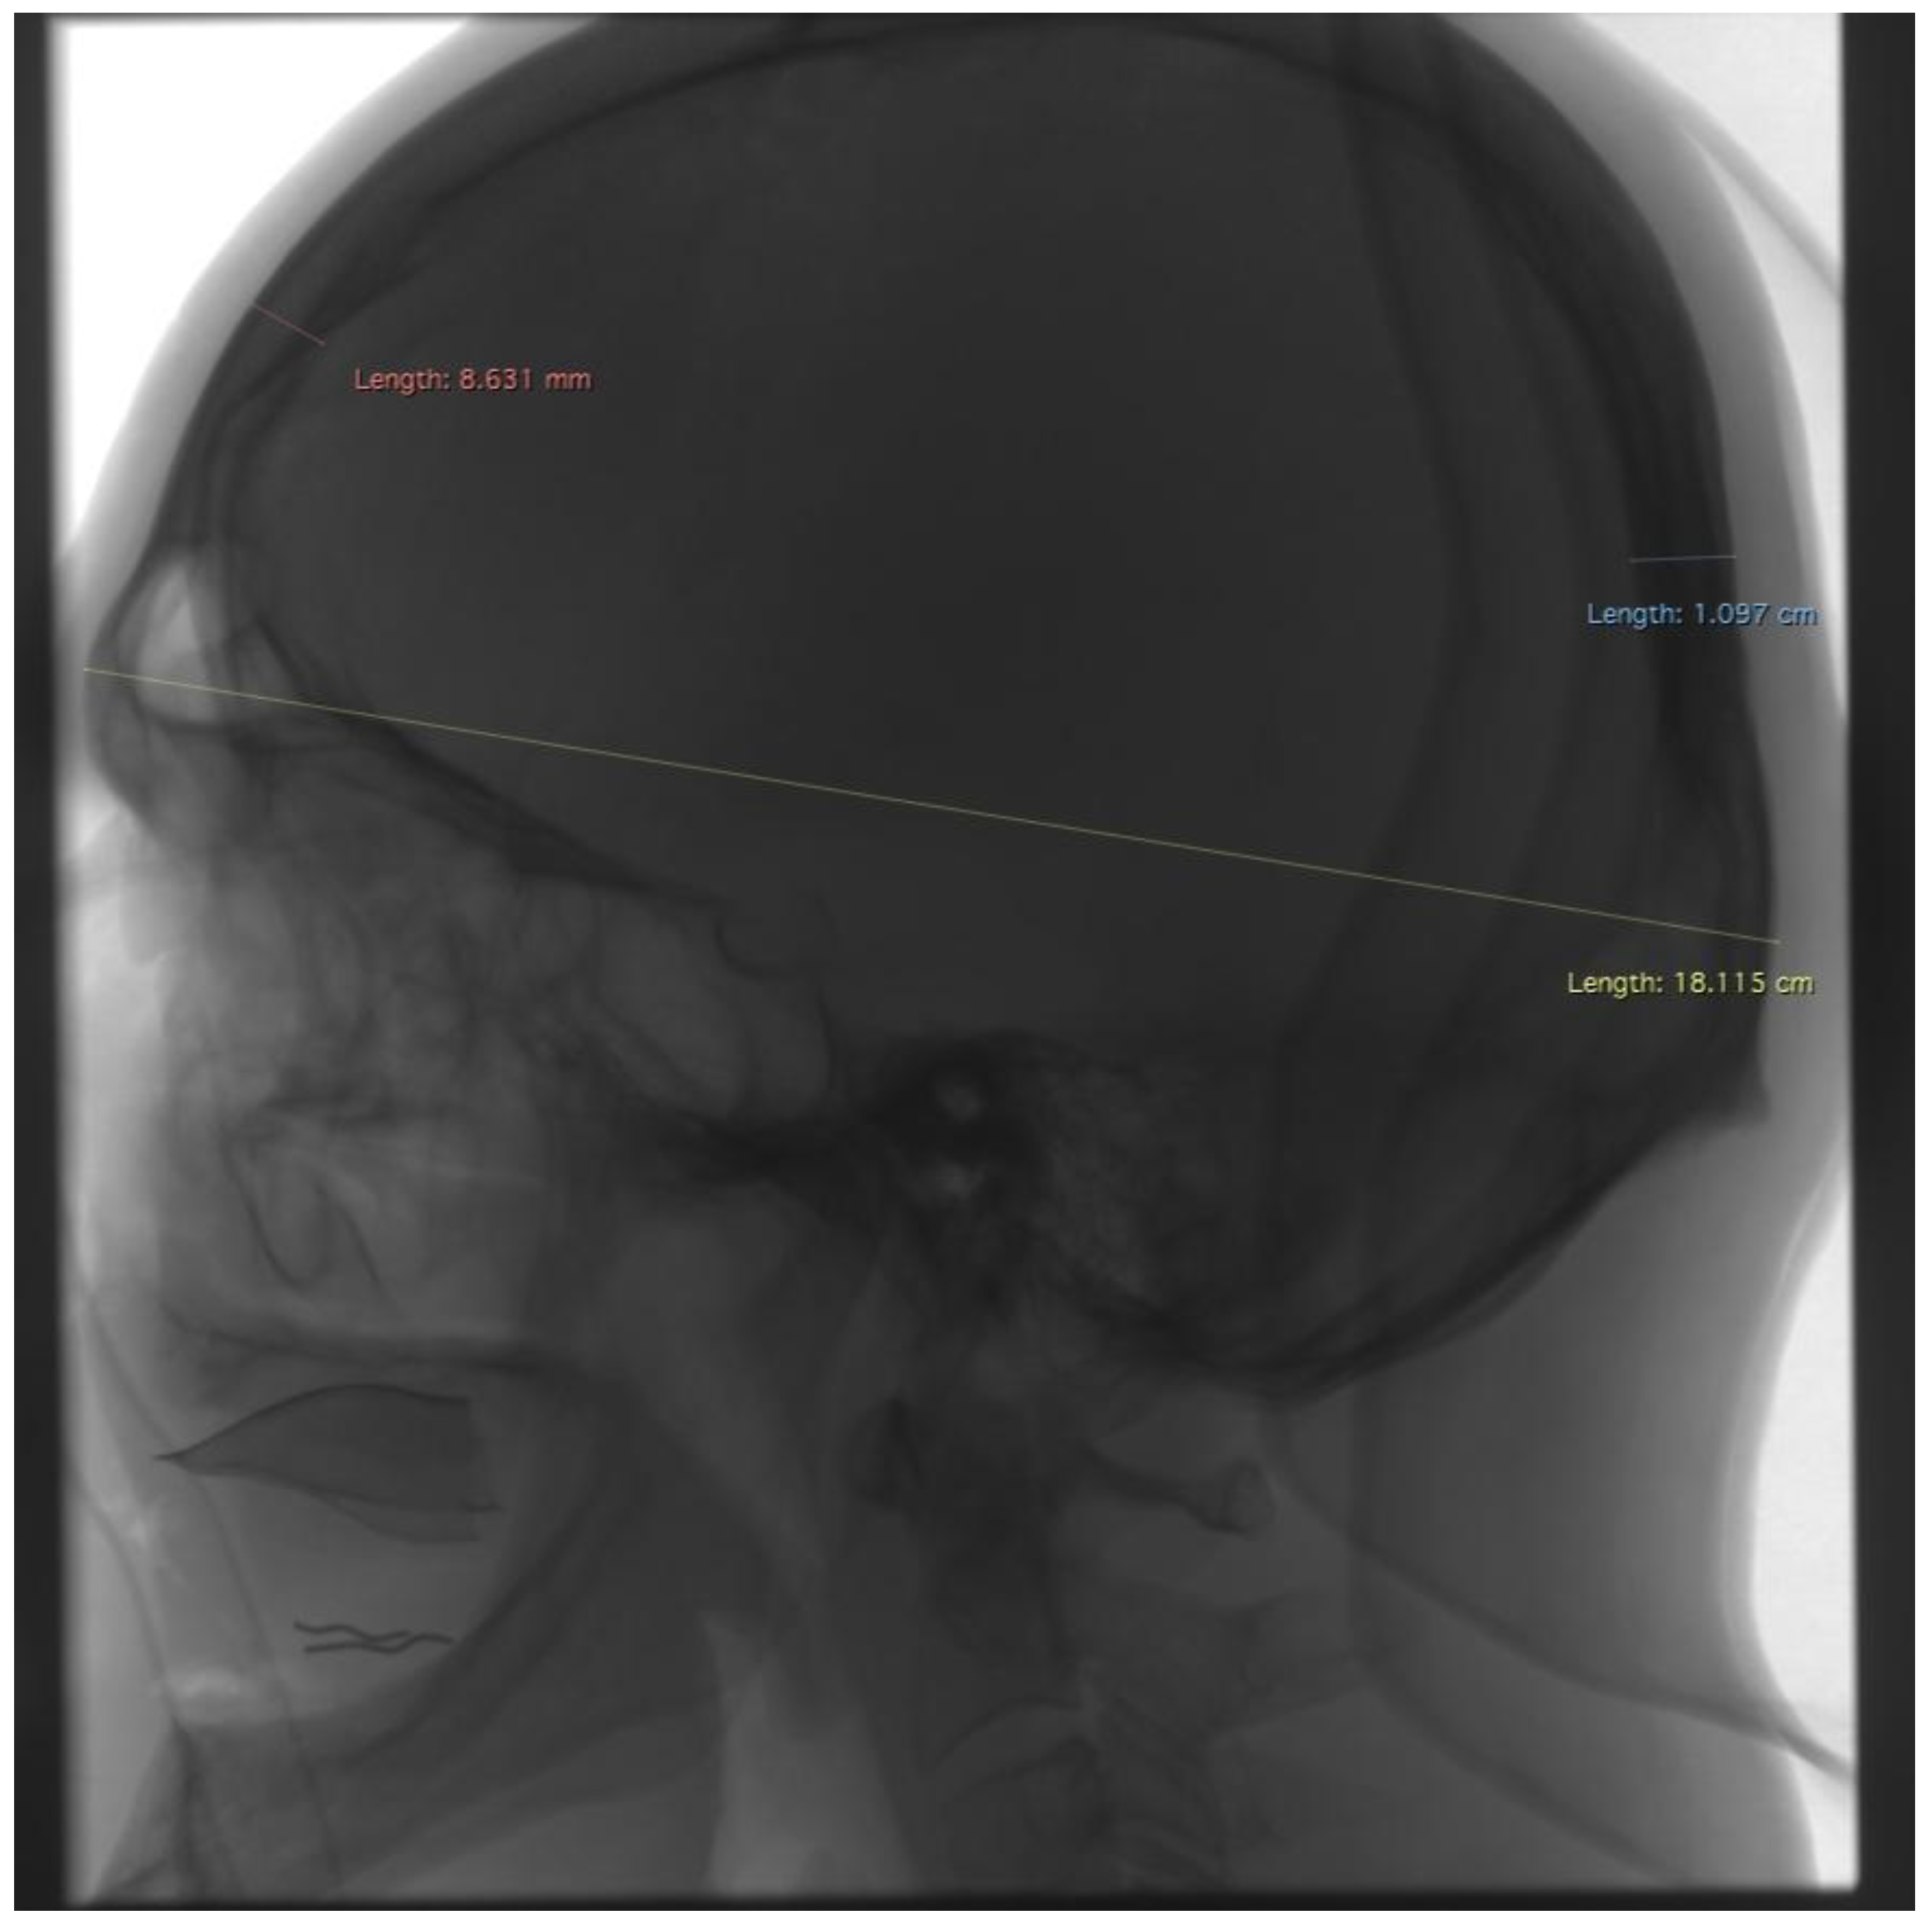

One center retrospectively analyzed medical records from a prospectively maintained database of patients who underwent DSA. All DSA examinations were performed between 31 January 2020 and 9 April 2021 in patients with suspected or confirmed central nervous system vascular aneurysms. Images were obtained using a GE Innova IGS 630 (GE HealthCare Technologies Inc., Chicago, IL, USA) C-arm biplanar angiosuite using the ARTERIOGRAPHY MO protocol. During the conducted examination, the following data were collected: gender, X-ray tube parameters (kV and mA), information about the rotation of the C-arm during the examination, the number of projections performed, information about the side of the examination (right/left/both sides), the presence or absence of metal coils (after a previous embolization procedure). Contrast injection rate, in our hospital, is typical for this exam. Value of the contrast is comparable in every data. This is the reason for why authors do not analyze these parameters. Using Horos software, cephalometric measurements were taken on radiographs in PA and lateral projections. Measurements included the widest cranial width (M8), the greatest cranial thickness near the points (eu, which is the beginning and end of the chord guided to delineate the M8 line) on both sides (Figure 1), the greatest cranial length (M1), and the greatest cranial thickness near the points (g and op, which are the beginning and end of the chord guided to delineate the M1 line) on both sides (Figure 2). A total of 251 patients (181 women, 70 men) were included. The number of unilateral DSA studies was 72 L and 64 P (136 in total). The number of bilateral DSA studies was 115. A total of 251 cephalometric measurements were taken, of which 6 parameters (M8, M1, 2× eu, op, and g) were measured in each study. The scheme of measurements is shown in Figure 1 and Figure 2. The collected data were subjected to statistical analysis using Statistica Statsoft V14.0 EN software and, in the Python environment, using the SciPy library, employing a series of statistical tests. For all analyses, the significance of results was assumed for p less than 0.05. Spearman’s rank correlation was used to analyze continuous data corresponding to successive dimensions (M8, eu, M1, g, and op) with voltage and current. The Mann–Whitney U test was used to analyze the correlation of nominal data (gender, coils) with X-ray tube parameters. Due to the presence of outliers, the dataset was cleaned by applying an interquartile cut-off to the analyzed variables. Thus, 27 records were excluded, leaving 224 measurements for the analysis of X-ray tube parameters.

Figure 1. Example of measurements taken in lateral projection. Red—the greatest cranial thickness near the point g, blue—the greatest cranial thickness near the point op, yellow—the greatest cranial length (M1).